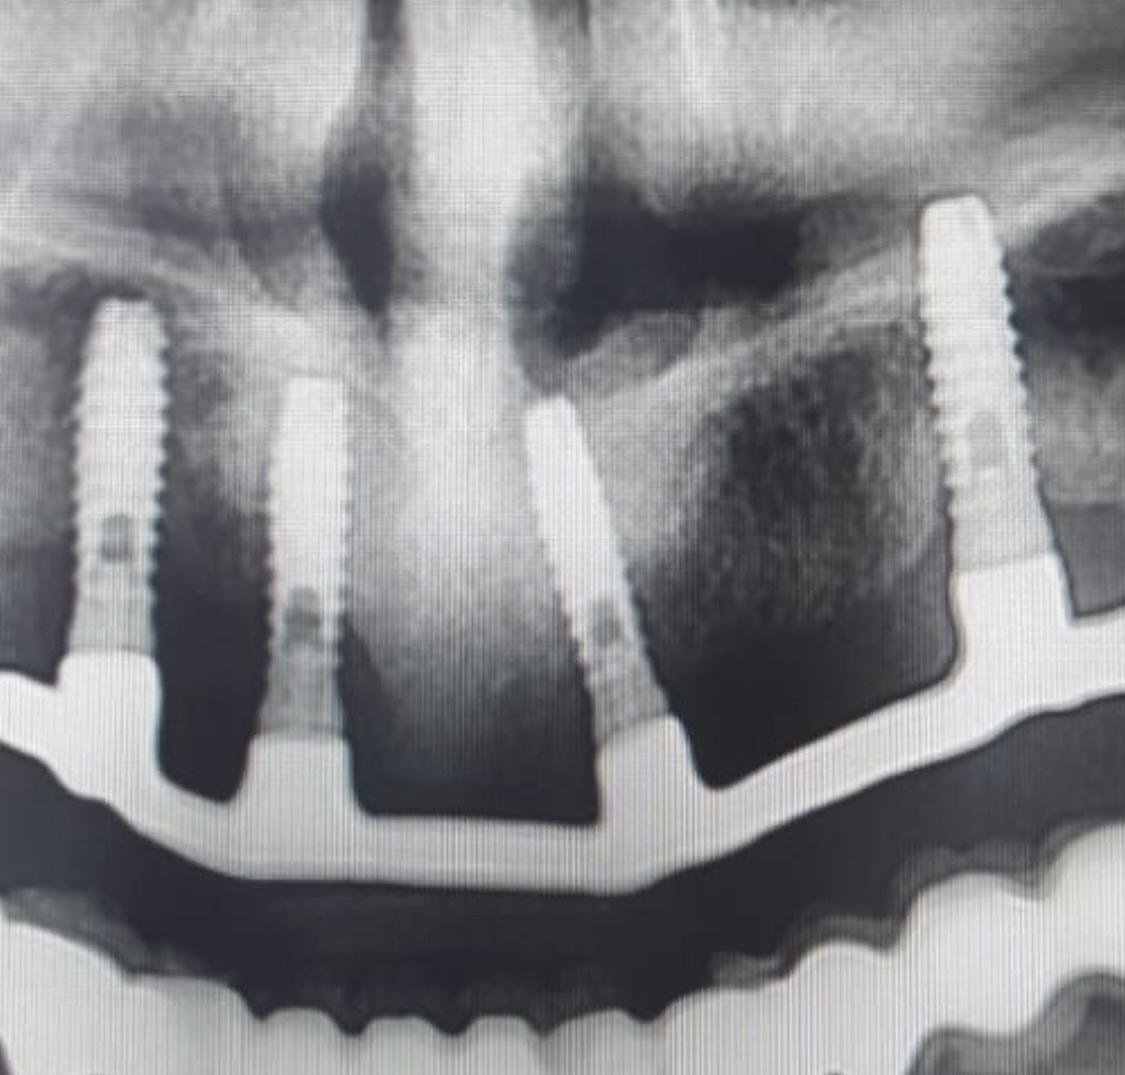

Son implantes Microdent de conexión externa. Microdent tiene 2 tipos de conexión externa, uno universal, compatible con Branemark, y otro no compatible, el System. Para poder saber cuál es, retira la estructura y prueba un aditamento de Branemark.